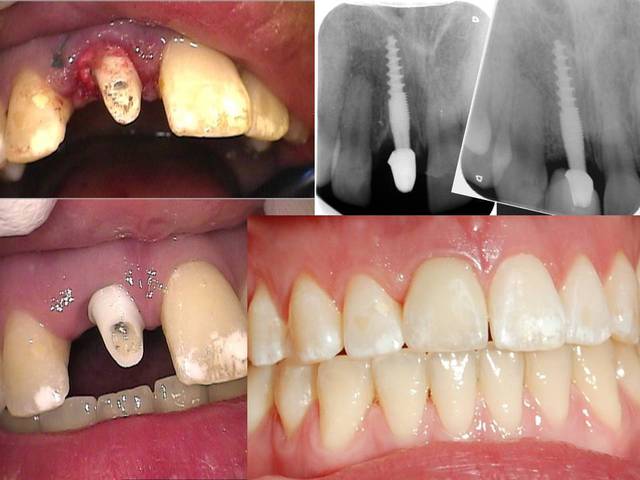

ci dessous quelques photos , schemas des implantations immédiates pour les incisives où tu peux creer une nouvelle alvéole grâce au foret jaune et condenseur spéciaux. Ainsi tu n as pas de collapse d alveoles en preservant le perioste.Si l espace entre l implant et le mur (ou paroi, je ne sais pas en francais?) buccal est supérieur à 1mm, j ajoute de la acide hyaluronique et quelques fois du collagène...

Les résultats sont enthousiasmants également après quelques années

Pour ceux que ca interessent, et parce qu on a m a demandé des cas supplémentaires dans le sujet 23 implants rehabilitation totale, voici un autre cas d implantation immédiate avec la technique minimalement invasive et condensation grace aux forets.

Le patient a reçu un traitement il y a dix ans dans le maxillaire et dans le 4eme quadrant.Comme on peut le voir j´ai du extraire quelques dents au maxillaire: 35 37 et 45.

Le septum de la 37 a été foré avec un foret conique 3 faces.

J ai planté à 60 Ncm sans fracturer le septum.Juste après l opération , les prep caps en zircon ont été cémenté.La restauration définitive 34 jusqu` à 37 été fixé 2 semaines après l implantation avec implantlink (detax). Après un an, le bridge a été retiré facilement pour voir l´état de la gencive et faire une radio de contrôle.On la re ossifiction est satisfaisante et que la gencive "aime" le zircon.

Le bridge a ensuite été recémenté sans correction nécessaire du bridge.